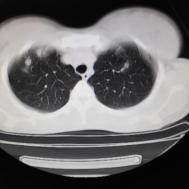

支原体肺炎1例CT影像表现

性别:女,年龄:26岁,低热,轻微胸痛,支原体阳性

两肺内及胸膜下多发斑片状高密度影,部分病灶密度较淡,部分实变,边缘可见渗出改变。

支原体肺炎是由支原体引起的以间质改变为主的肺炎。实验室检查支原体抗体呈阳性。支原体侵入肺内可引起支气管、细支气管黏膜及其周围间质充血、水肿,多核细胞浸润,侵入肺泡可产生肺泡浆液性渗出性炎症。CT早期主要改变为肺间质炎症,病变区肺纹理增粗而模糊,病变范围广泛,常累及多个肺叶,单侧或双侧的磨玻璃影及实变影,以双肺下叶多见,多呈小叶性分布。同时,患者的临床症状与CT改变不匹配,即临床症状明显好转或消失但肺部阴影吸收不明显。鉴别诊断:支气管肺炎好发于两中下肺的内、中带,病灶沿支气管分布,呈多发散在小的斑片状影,常合并阻塞性小叶性肺气肿或小叶性肺不张,结合临床多见于婴幼儿或年老体弱者。渗出浸润为主的继发性肺结核病灶表现为结节状或呈不规则斑片状影,边缘较模糊,密度不均匀,病灶内可见小空洞。增殖性病灶密度较高,边缘清楚,病灶内或周围可见不规则钙化灶。浸润性病变常与纤维化并存,可伴有邻近支气管扩张。结核分枝杆菌检查阳性。